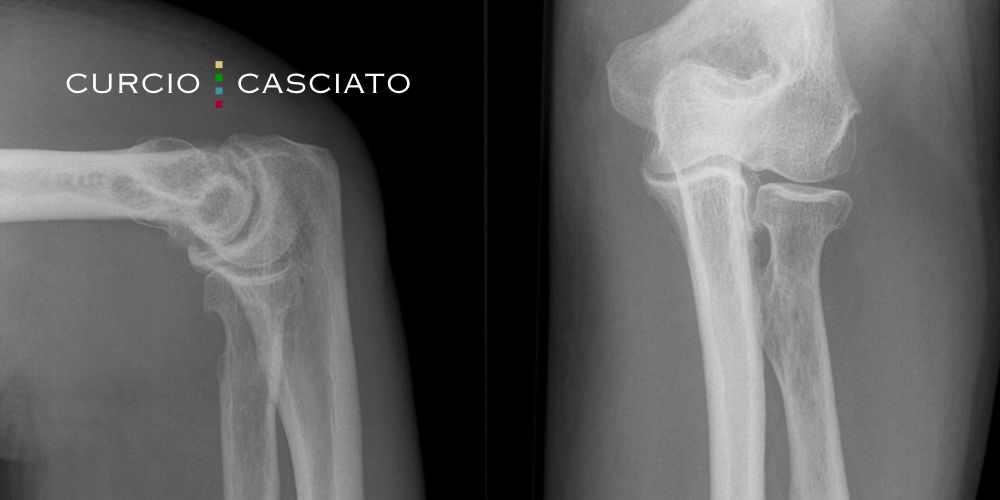

To increase your chances of proving nursing home abuse and neglect, it is important to gather as much evidence as possible. Our team will obtain medical records that show your loved one’s overall health before and after the accident or injury. X-rays and incident reports help document the type and timing of the broken bone. Expert witnesses can testify regarding proper fall-prevention standards and injury causes. We review staffing records to determine whether the home had sufficient workers on duty. State inspection reports from the IDPH often reveal safety violations and prior problems.